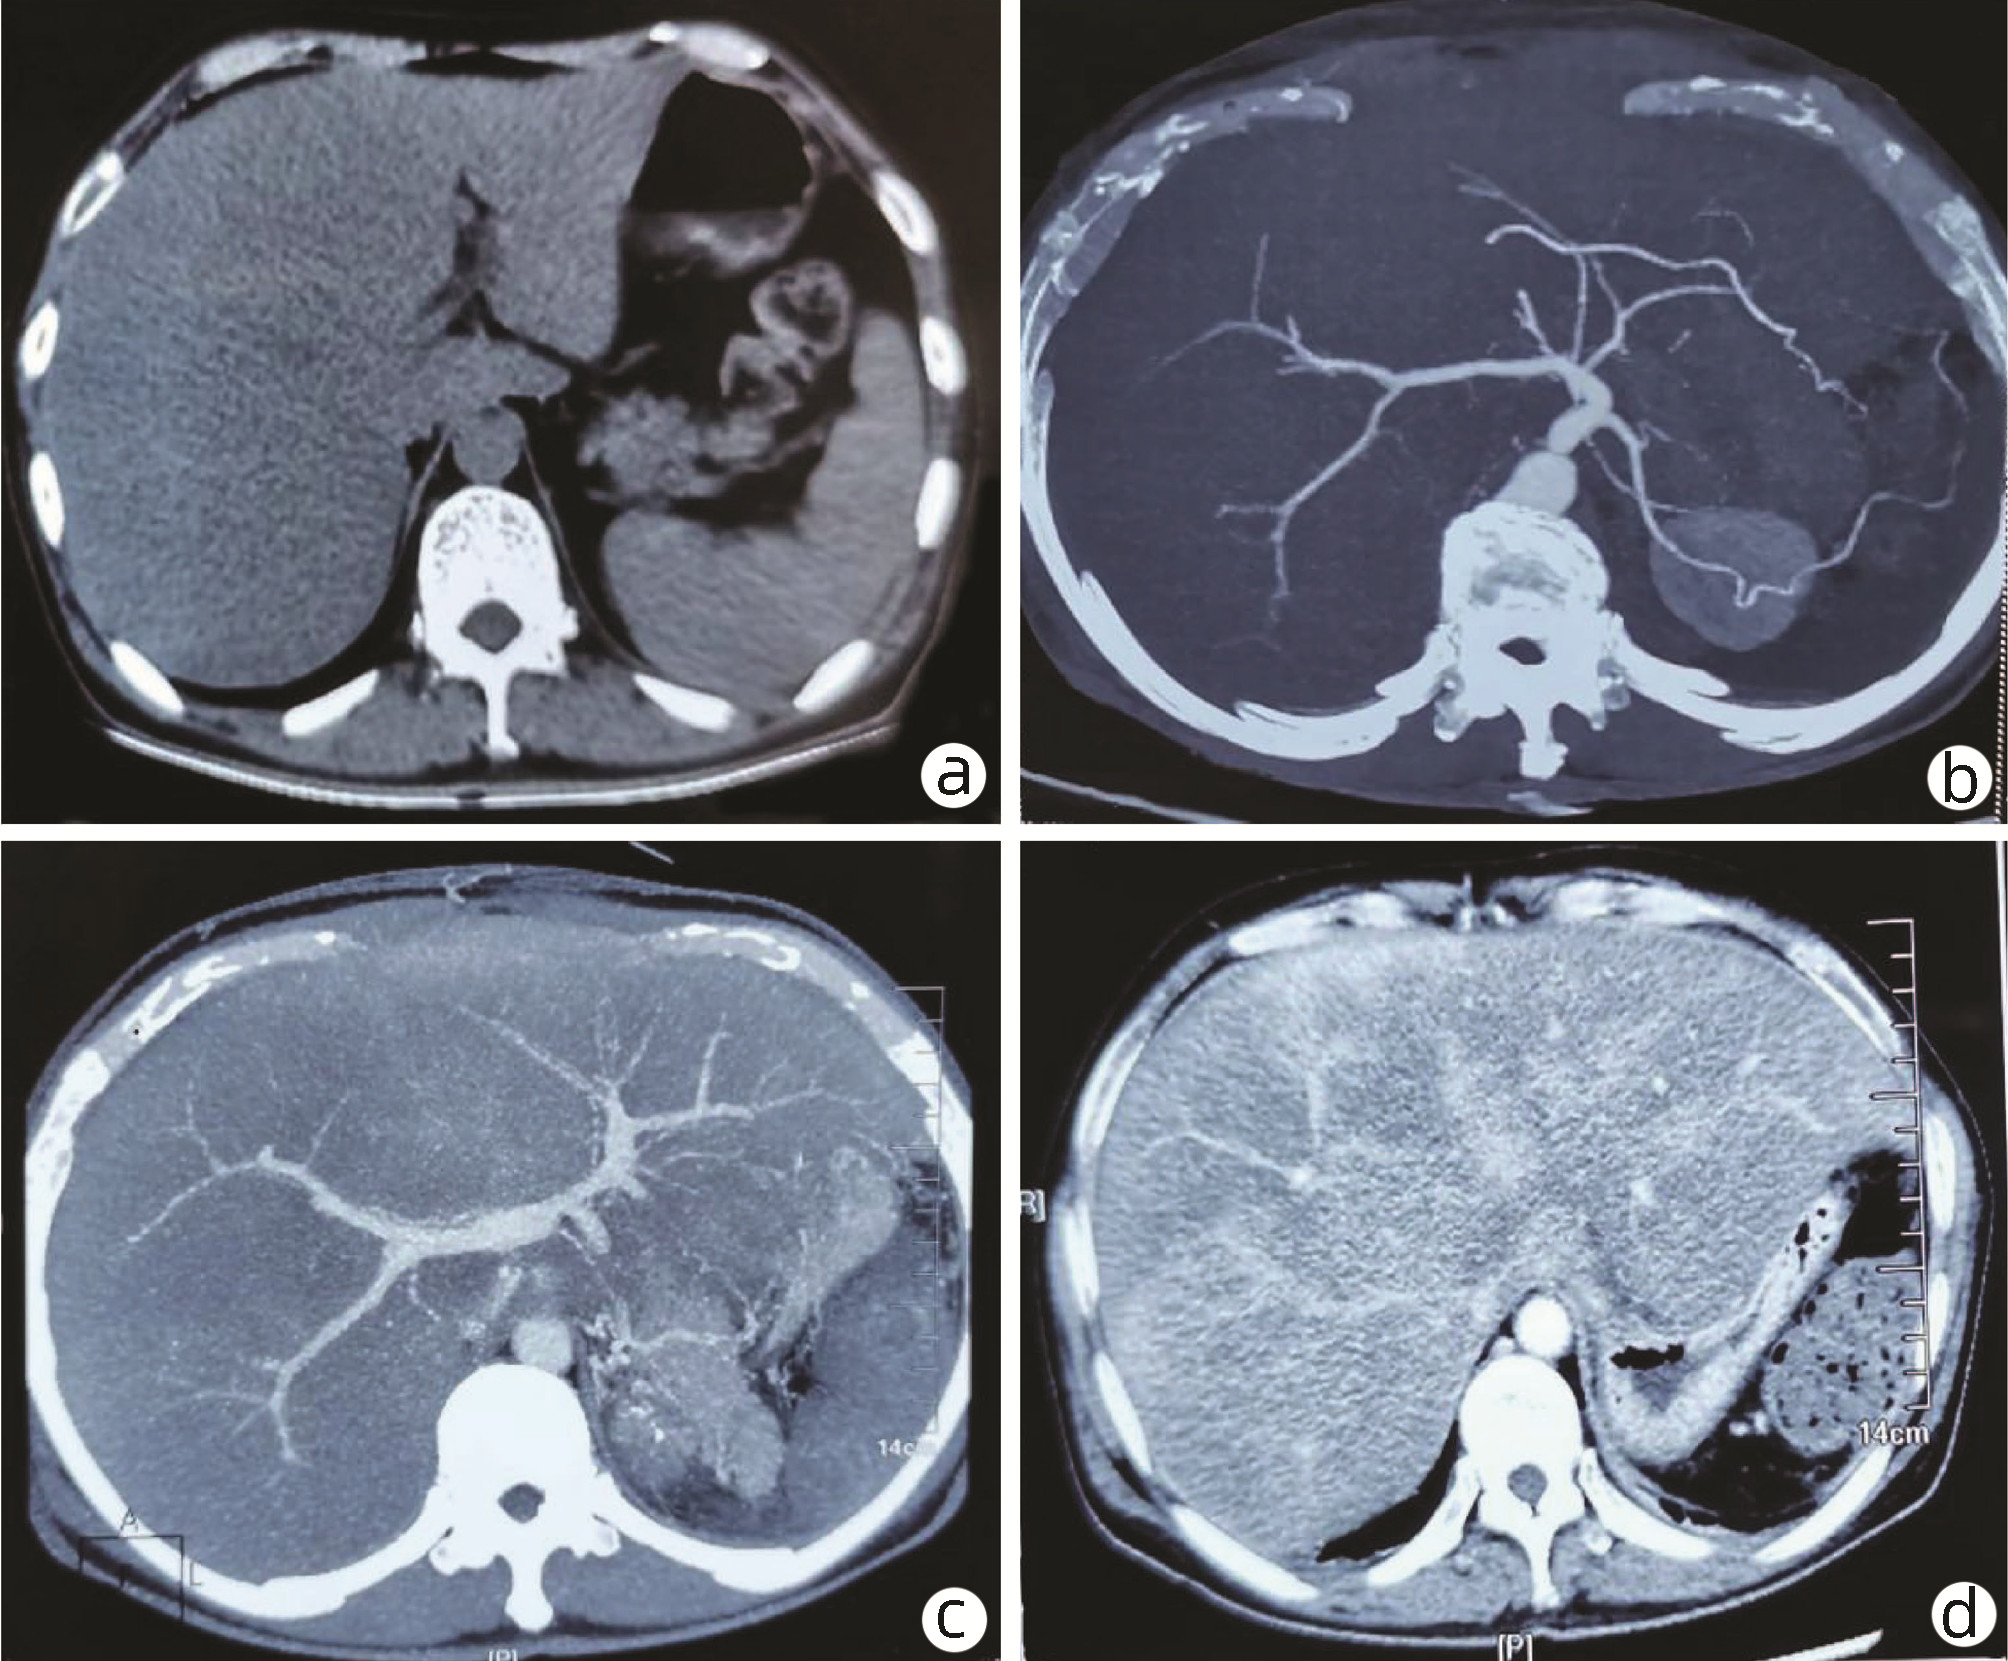

10例儿童肝糖原累积病临床及病理学分析

赵素贤, 刘世恒, 李文聪, 韩芳, 刘树红, 张庆山, 任伟光, 孔令波, 付娜, 王荣琦, 孔丽, 南月敏, 赵景民

2022, 38(8): 1839-1842. DOI: 10.3969/j.issn.1001-5256.2022.08.022

摘要(1407) HTML (512) PDF (2394KB)(109)

摘要:

目的  探讨儿童糖原累积病(GSD)的临床及病理学特点。  方法  选择2002年1月—2022年1月河北医科大学第三医院及解放军第五医学中心经病史、肝脏生化及肝活组织检查确诊的GSD 10例,对比分析人群特征、临床表现、生化指标、肝组织病理学特点。  结果  10例患儿发育迟缓,矮小,均表现为肝功能异常,轻度乏力、纳差、尿黄、眼黄,4例患者肝脾肿大。6例患者有低血糖的临床表现;1例患儿双侧腓肠肌肥大,Gower征阳性。2例患儿巨细胞病毒IgG阳性。肝组织病理学表现肝细胞弥漫性肿大,胞浆空淡,核小居中似植物细胞状,伴或不伴纤维组织增生。  结论  GSD患者多数有发育迟缓、转氨酶异常,肝组织病理检查有其特异性病理特征。